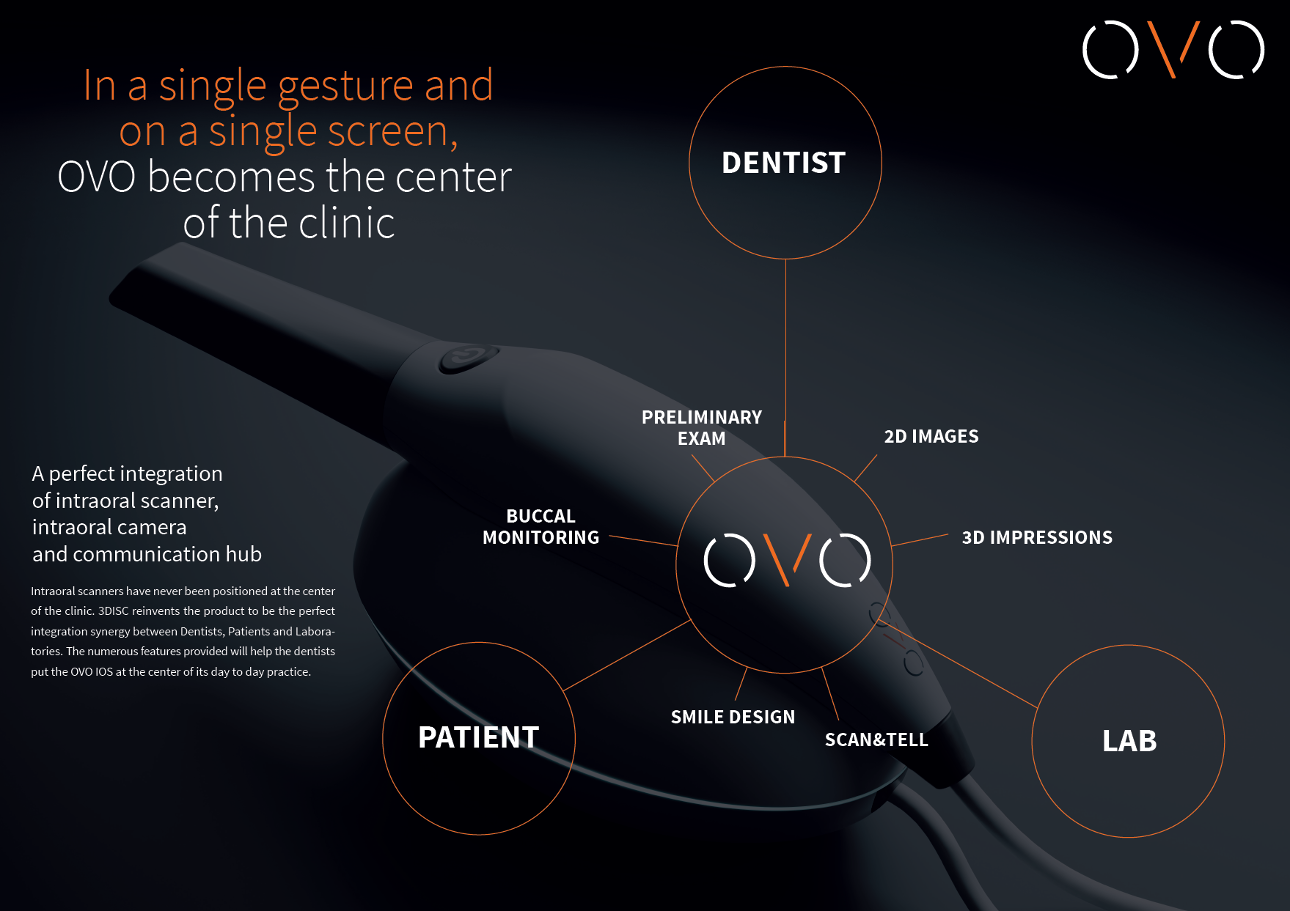

In one action, all your imaging needs : 3D scans, 2D images & videos intelligently sorted and displayed. Intraoral scanners have never before been positioned at the center of the clinic.

3DISC reinvents the concept, providing perfect integration synergy between Dentists, Patients and Laboratories. Our new range of features will help dentists put the OVO IOS at the center of their day-to-day practice.

A perfect integration of intraoral scanner,

intraoral camera and communication hub

Intraoral scanners have never been positioned at the center of the clinic. 3DISC reinvents the product to be the perfect integration synergy between Dentists, Patients and Laboratories. The numerous features provided will help the dentists put the OVO IOS at the center of its day to day practice.